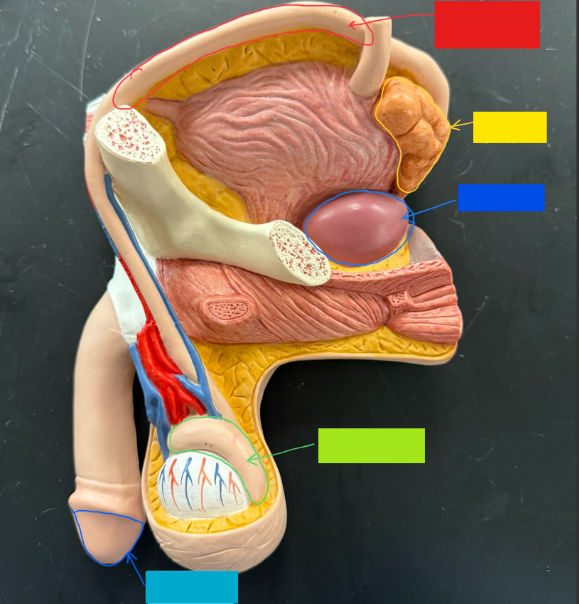

What is the name of the red box?

Ureter

What is the name of the yellow box?

Seminal vesicle

What is the name of the blue box?

Prostate

What is the name of the light green box?

Epididymis

What is the name of the light blue box?

Prepuce